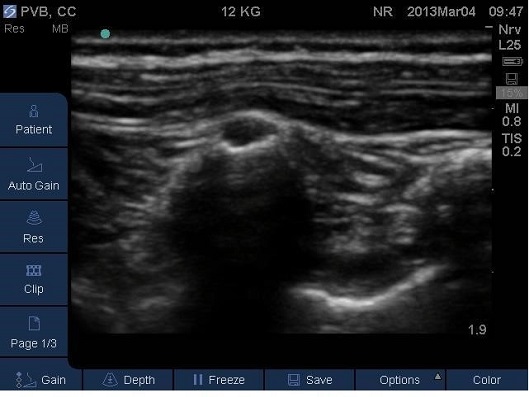

- Correct placement of the needle in the thoracic Paravertebral space should be confirmed by the anterior displacement of pleural upon injection of a small bolus of saline or local anaesthetic (Fig 13-16).

Fig 13.